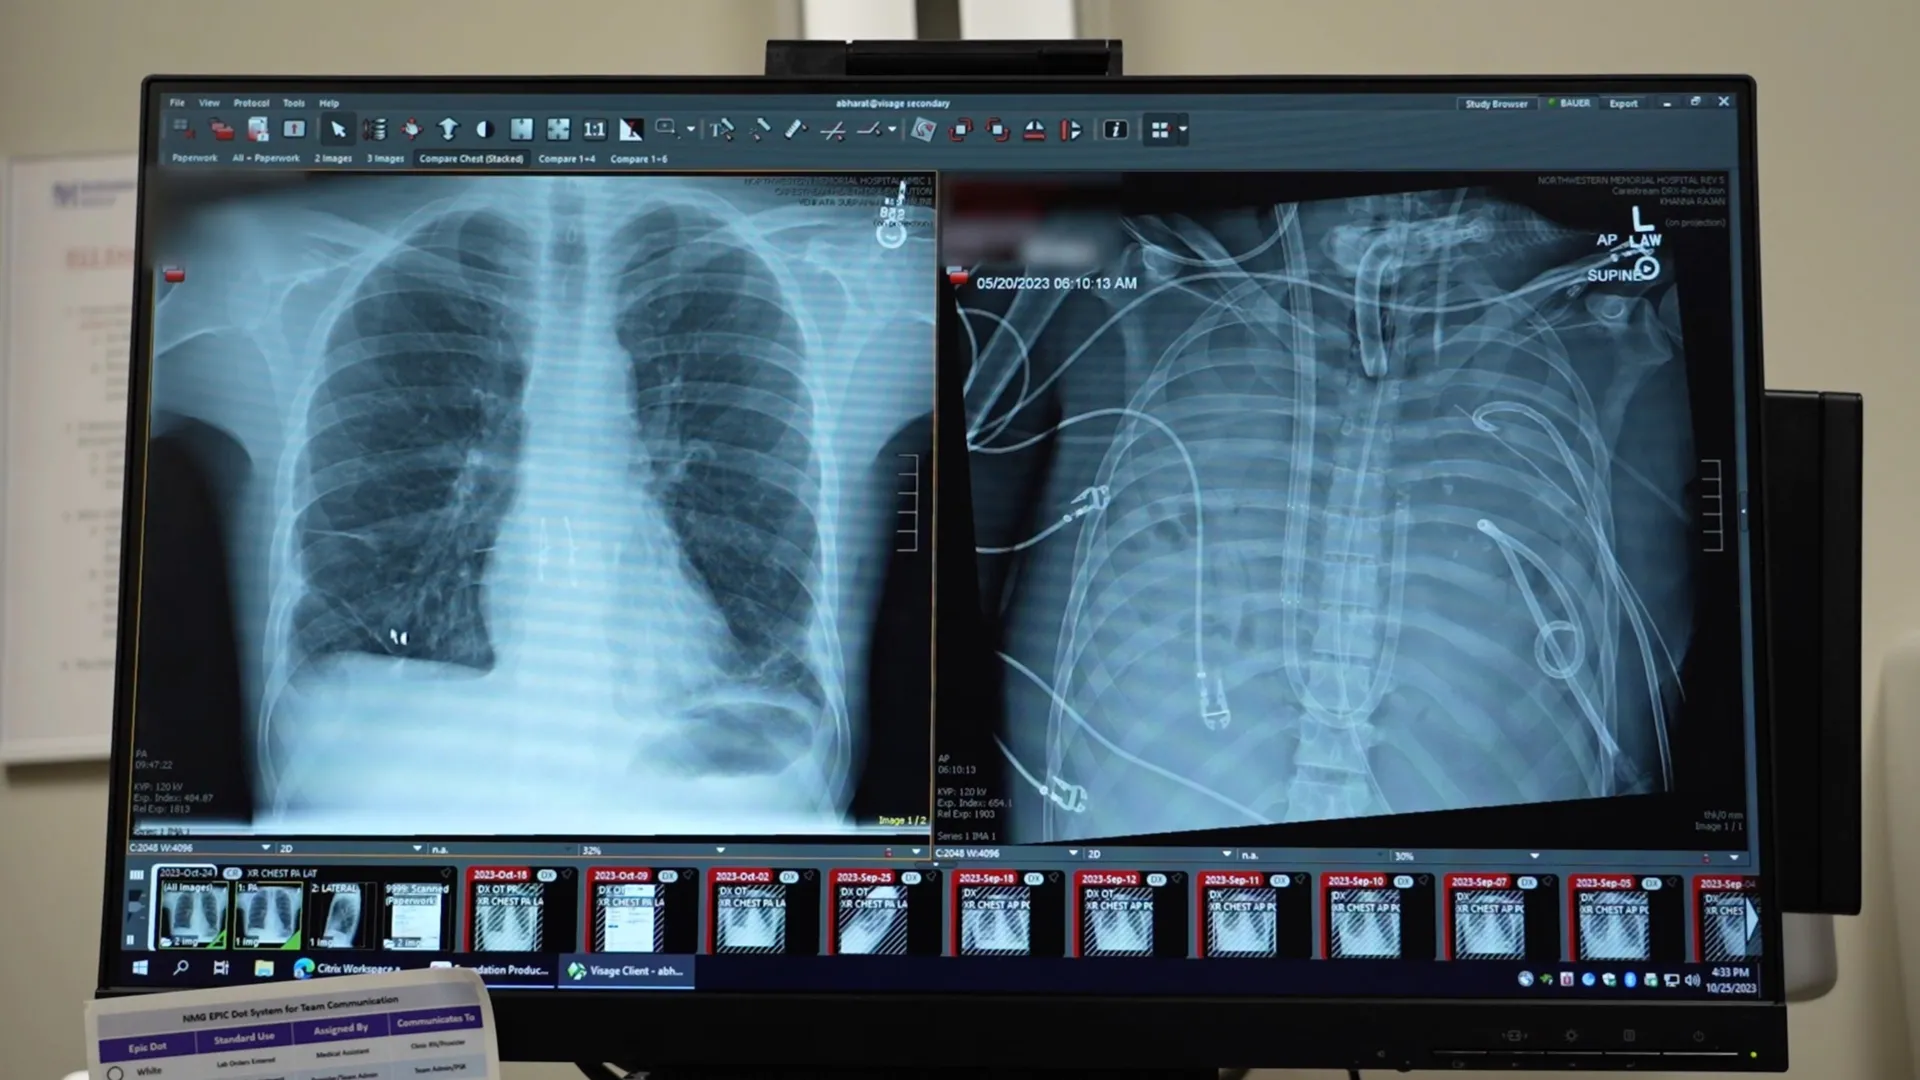

Em um relatório publicado no Cell Press Journal Dr. comOs cirurgiões detalharam como removeram o pulmão gravemente infectado de um homem e usaram um sistema de “pulmão artificial” para mantê-lo vivo até que um transplante duplo de pulmão pudesse ser realizado. O caso destaca uma nova forma potencial de manter vivos pacientes terminais enquanto esperam por um doador de órgão.

O paciente, um homem de 33 anos, tinha síndrome do desconforto respiratório agudo (SDRA), uma condição perigosa em que inflamação e infecção tomam conta dos pulmões. Sua doença começou com uma gripe, que piorou rapidamente e foi complicada por uma pneumonia bacteriana. À medida que sua condição piorou, seus pulmões, coração e rins começaram a falhar. Nesse ponto, um transplante duplo de pulmão tornou-se sua única chance de sobrevivência.

Os pulmões do homem estavam além da preservação e contribuíam ativamente para a propagação da infecção. No entanto, seu corpo estava instável demais para realizar um transplante imediatamente, então os médicos precisaram de tempo para estabilizá-lo.

Para combater isso, as equipes médicas desenvolveram um sistema pulmonar artificial projetado para assumir temporariamente o papel de pulmão. Este sistema oxigena o sangue, remove o dióxido de carbono e apoia a circulação, permitindo que o coração e outros órgãos continuem a funcionar mesmo quando o paciente não tem pulmões.

Após a remoção do pulmão afetado, a condição do paciente começou a melhorar. Sua pressão arterial se estabilizou, seus órgãos começaram a se recuperar e a infecção foi controlada. Dois dias depois, um doador de pulmão foi encontrado e os cirurgiões concluíram com sucesso um transplante duplo de pulmão. Mais de dois anos depois, o paciente leva uma vida normal com função pulmonar saudável.